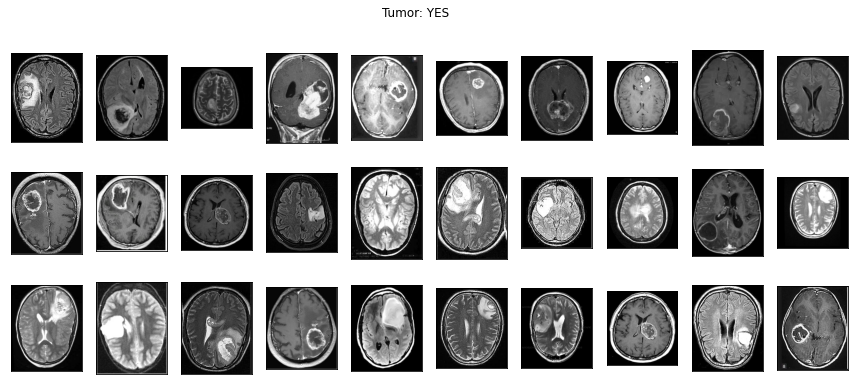

아울러 일반적인 사진 이외에 의료영상도 이미지 분석이 가능해요. 의료영상은 DICOM(Digital Imaging and Communications in Medicine) file(확장자 .dcm)로 저장되어 있어요. 'Digital' 즉, 숫자 형식으로 되어있기에 이미지 분석이 가능해요. 아래의 이미지는 뇌종양을 진단하기 위한 MRI 이미지예요!

이 이미지를 이용해서 뇌종양을 예측하는 알고리즘을 아래에서 실습해볼테니 끝까지 봐주세요!

양성 1500개, 음성 1500개인 균등한 데이터를 준비해서 <Image Reader>로 읽었어요. ‘yes’ 주석이 있는 윗줄이 양성 이미지이고 ‘no’ 주석이 있는 아랫줄이 음성 이미지에요.